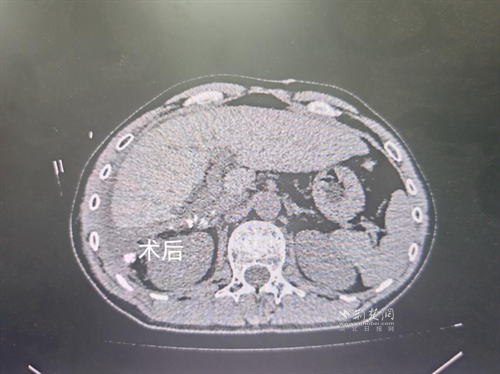

經(jīng)過肝膽外科牽頭組織的多學(xué)科MDT會(huì)診,團(tuán)隊(duì)確認(rèn)其適合接受當(dāng)前國際先進(jìn)的釔90樹脂微球選擇性內(nèi)放射治療。治療僅一個(gè)月后,患者病灶即從10cm縮小至6cm;術(shù)后六個(gè)月復(fù)查顯示,病灶體積進(jìn)一步縮小近40%,影像學(xué)檢查提示完全緩解,臨床分期成功轉(zhuǎn)化,達(dá)到手術(shù)切除標(biāo)準(zhǔn)。